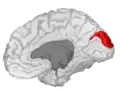

![]() Medial surface of left cerebral hemisphere. (Cuneus visible at left in red.) | |

The cuneus (from Latin 'wedge'; pl.: cunei) is a smaller lobe in the occipital lobe of the brain. The cuneus is bounded anteriorly by the parieto-occipital sulcus and inferiorly by the calcarine sulcus.

Position of cuneus(red) of left cerebral hemisphere. -